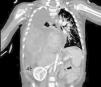

Se decide completar el estudio con ecografía y tomografía axial computarizada (TAC), evidenciándose hernia diafragmática derecha (HDD) con lóbulo hepático derecho (LHD) incarcerado con ascitis, vía biliar dilatada y venas suprahepáticas y cava inferior suprarrenal colapsadas con circulación venosa colateral (fig. 2).